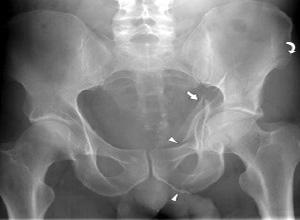

髋臼骨折大多数是由股骨头受到外界暴力传导引起的,常会遗留以下三种并发症:

创伤后关节炎是髋臼骨折的远期并发症,多见于髋臼上臂骨折和髋关节后脱位。其发生原因与股骨头承重面骨折、永久性关节半脱位、关节面不对称等因素有关,手术治疗时尽量恢复良好的解剖复位,尤其是髋臼负重面的解剖复位可以有效的降低创伤后关节炎的发生率。